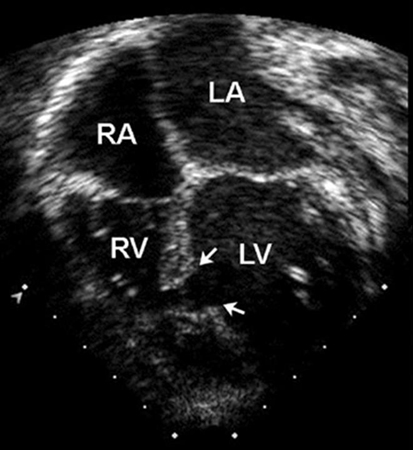

Peri-membranous defects typically occur as a solitary lesion and can sometimes close spontaneously by apposition of the septal leaflet of the tricuspid valve to the defect. Outlet defects may be large and associated with more complex forms of congenital heart disease such as tetralogy of Fallot. Both peri-membranous and outlet VSDs are in close proximity to the right cusp of the aortic valve. Because of the Venturi effect, these defects can cause prolapse of an aortic valve cusp, which results in both a restriction to flow through the VSD and regurgitation of the aortic valve.[22] Inlet defects do not close spontaneously and may be associated with AVSD and AV valve regurgitation. Muscular defects are the most common type of VSDs in newborns and the vast majority close spontaneously before 2 years of age.[Figure caption and citation for the preceding image starts]: Apical 4-chamber echocardiographic image of a muscular VSD (arrow). (RA) right atrium; (LA) left atrium; (RV) right ventricle; (LV) left ventricleImage courtesy of Patrick W. O'Leary, MD [Citation ends].